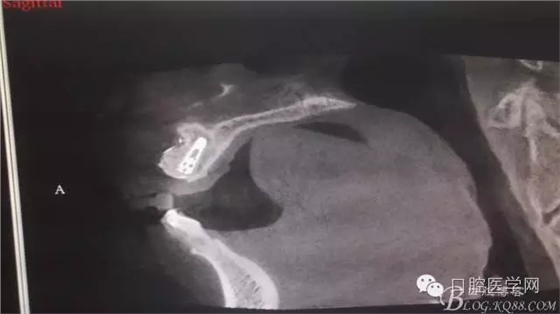

植入種植體左側(cè)3510,右側(cè)4010,植骨Bioss,蓋膜Cytoplast。骨膜減張垂直褥式縫合加間斷縫合。

之所以選擇Bioss是考慮其降解速度較慢,種植體接觸大面積為自體骨,Bioss可以很穩(wěn)定的緩慢吸收逐步引導(dǎo)骨再生。

后期的修復(fù)工作由之前的轉(zhuǎn)診醫(yī)生后續(xù)處理,由于GBR過(guò)程骨膜減張導(dǎo)致角化牙齦不足3mm,建議角化牙齦移植改變其更好的牙齦生物型。